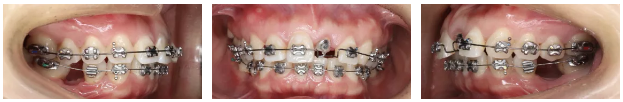

第二阶段:正畸修复联合治疗

—粘接矫治器,合向牵引21

—上颌拔除14、24,右上采用中等支抗内收关闭间隙,左上强支抗

—下颌弱支抗关闭间隙(前牙3D打印舌侧夹板)

—21树脂冠确定近远中径,粘接矫治器对其转矩精细调整

—21颊腭侧牙周修整